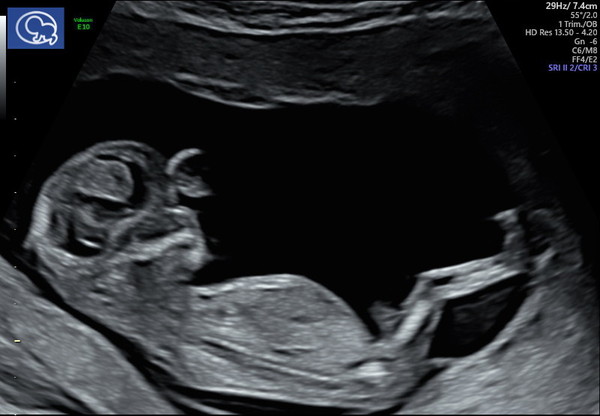

This is my DC4, everything going well so far, had my 12 week scan last week, due date 19th May :-) baby looked to be growing well but my free HcG came back 4x higher than it should be and made the risk for trisomy 21 quite high so I will need a CVS. Nuchal fold measurement was ok though, so fingers crossed all is well. I'm not in the UK so my antenatal care is a bit different, it's all with a doctor who I see once a month and have regular scans which is very reassuring! My 12 week scan was so thorough, so different to the experience in the UK!

It's lovely to see so many scan photos!